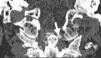

Axial skeleton affection due to chondrocalcinosis has been associated to calcium deposits in the intervertebral disc, the yellow ligament, the fact joints and even the sacroiliac joints. Calcification of the transverse ligament of the atlas (Figs. 1–3) is an infrequent manifestation and has been denominated the Crown Dens syndrome. It mostly constitutes an asymptomatic clinical picture but may be associated with episodes of acute cervical pain, stiffness and fever, with the added diagnostic difficulties of these cases.

X-ray studies show cervical spondyloarthritis and calcification of the transverse ligament of the atlas and winged ligaments of the atlas-axis joint (Fig. 4).

The Crowned Dens syndrome was described initially in 1985 by Bouvet et al.1,2 Diagnosis is based on the association of a compatible clinical picture and imaging findings, mainly calcium deposits in atlas-axis joint ligaments, visible on CT.3,4